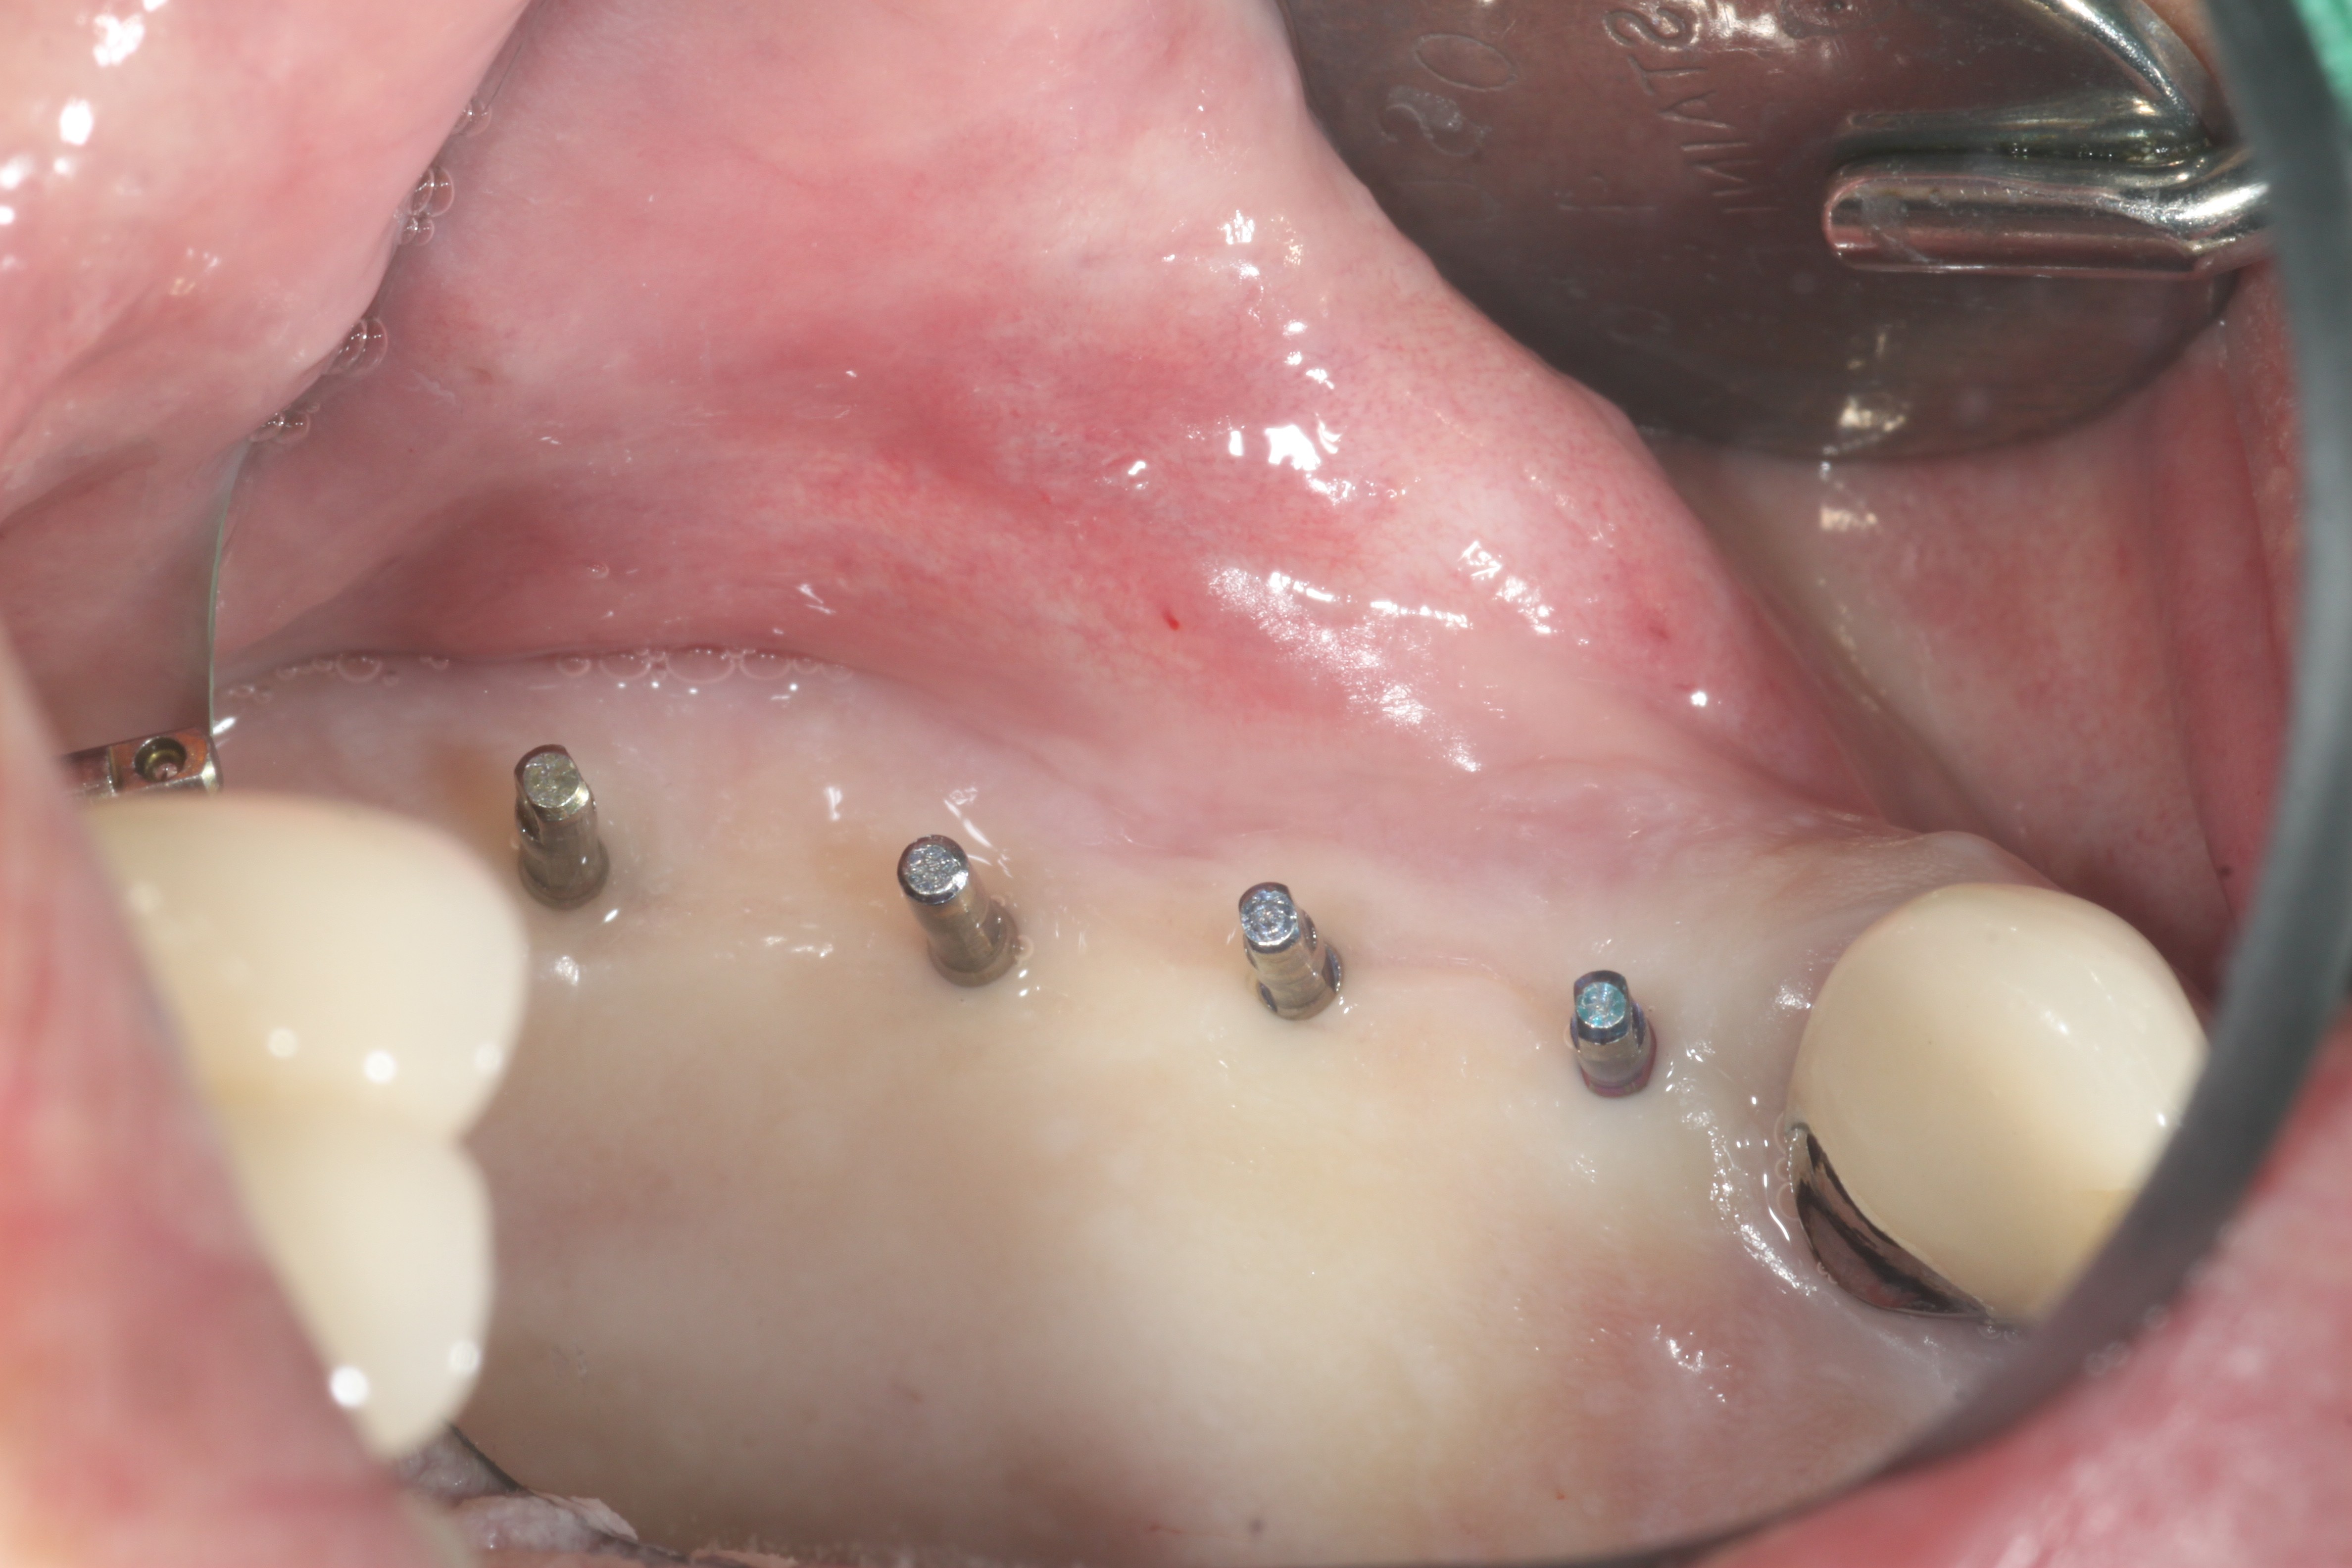

¿ì¼± óÀ½ °¡À̵å ÇÉÀ» ³Ö°í ÂïÀº »çÁøÀÔ´Ï´Ù, À̶§ ½ÃƼ¸¦ Âï¾î À§Ä¡¿Í »ÀÀÇ ³ôÀ̸¦ È®ÀÎÇÕ´Ï´Ù.

ÀÓÇöõÆ®¸¦ ½Ä¸³ÇÏ¿´À¾´Ï´Ù.

ȯÀÚºÐÀÌ ³Ê¹« ÆíÇϽôٰí ÇÕ´Ï´Ù.Çǰ¡ ¾È³ª°í¿ä.

½Ã¼ú½Ã ÀÕ¸öÀ» ¾à°£ Á¦°ÅÇϱ⿡ ±×¶§ ÇǸ¦ Á¶±Ý º¼¼ö ÀÖÁö¸¸ °ú´ÙÃâÇ÷À̳ª ½ÉÇÑ ¹ÝÀÀÀº ÀϾÁö ¾ÊÀ¾´Ï´Ù.